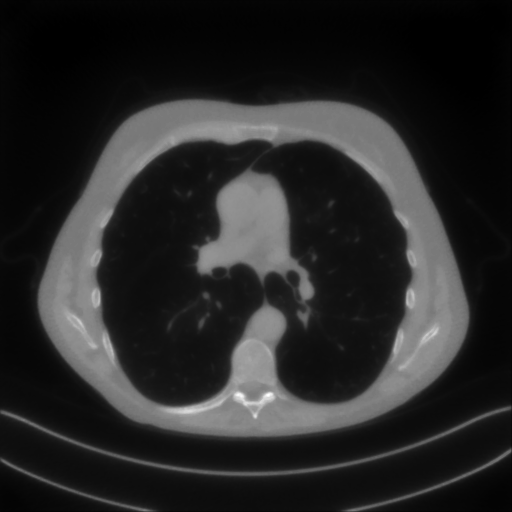

We now consider the CT protocol whose results are reported in Figure 6.

In this case, the tomographic reconstruction is more challenging than in the previous experiment. The starting image has evident streaking artifacts and blur and some details are lost, especially in the first zoom. The artifacts are reduced in the (top right image), where some details are recovered and the edges are quite neat.

The image obtained with the proposed RISING (bottom right) is visually an excellent reconstruction. It is very similar to the image, whose training, we remark, is based on more informative target images.

In Figure 7 we plot for these experiments, the same profiles of Figure 5.

In the left graph, we analyse the performance of LPP approach: the reconstruction gets values quite close to the GT, but it does not fit well the target black line.

In the right graph, we analyse the performance of RISING approach: the solution almost overlaps the target profile, confirming that the network has correctly learned.

At last we underline that the solutions of the CS regularized model are very similar in case of and geometries.